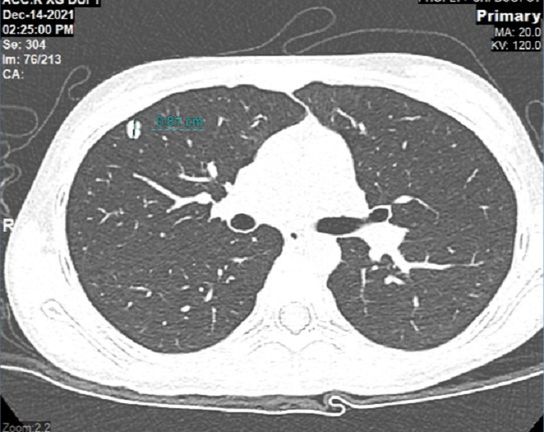

Hình chụp CT phối của cháu Khánh Thơ phát hiện khối u di căn phổi sau 1 năm phẫu thuật cắt bỏ u khớp gối.

Cháu Khánh Thơ, 12 tuổi phát hiện ung thư xương chày chân trái giai đoạn 2B từ giữa năm 2021. Sau khi phẫu thuật cắt bỏ toàn bộ khối u ở khớp gối, bảo tồn chi, cháu điều trị hóa chất bổ trợ 4 chu kỳ. Tuy nhiên, chỉ hơn 1 năm sau, bé Thơ đã di căn phổi.

Tìm hiểu về quá trình điều trị của bệnh nhân, GS.TS.BS Trần Trung Dũng - GĐ Trung tâm Chấn thương Chỉnh hình và Y học thể thao (CTCH) Vinmec cho biết, mặc dù bệnh nhân có kết quả mổ rất tốt, nhưng sử dụng hóa trị bổ trợ không đủ liều là nguyên nhân dẫn đến di căn phổi nhanh như nhiều trường hợp khác.